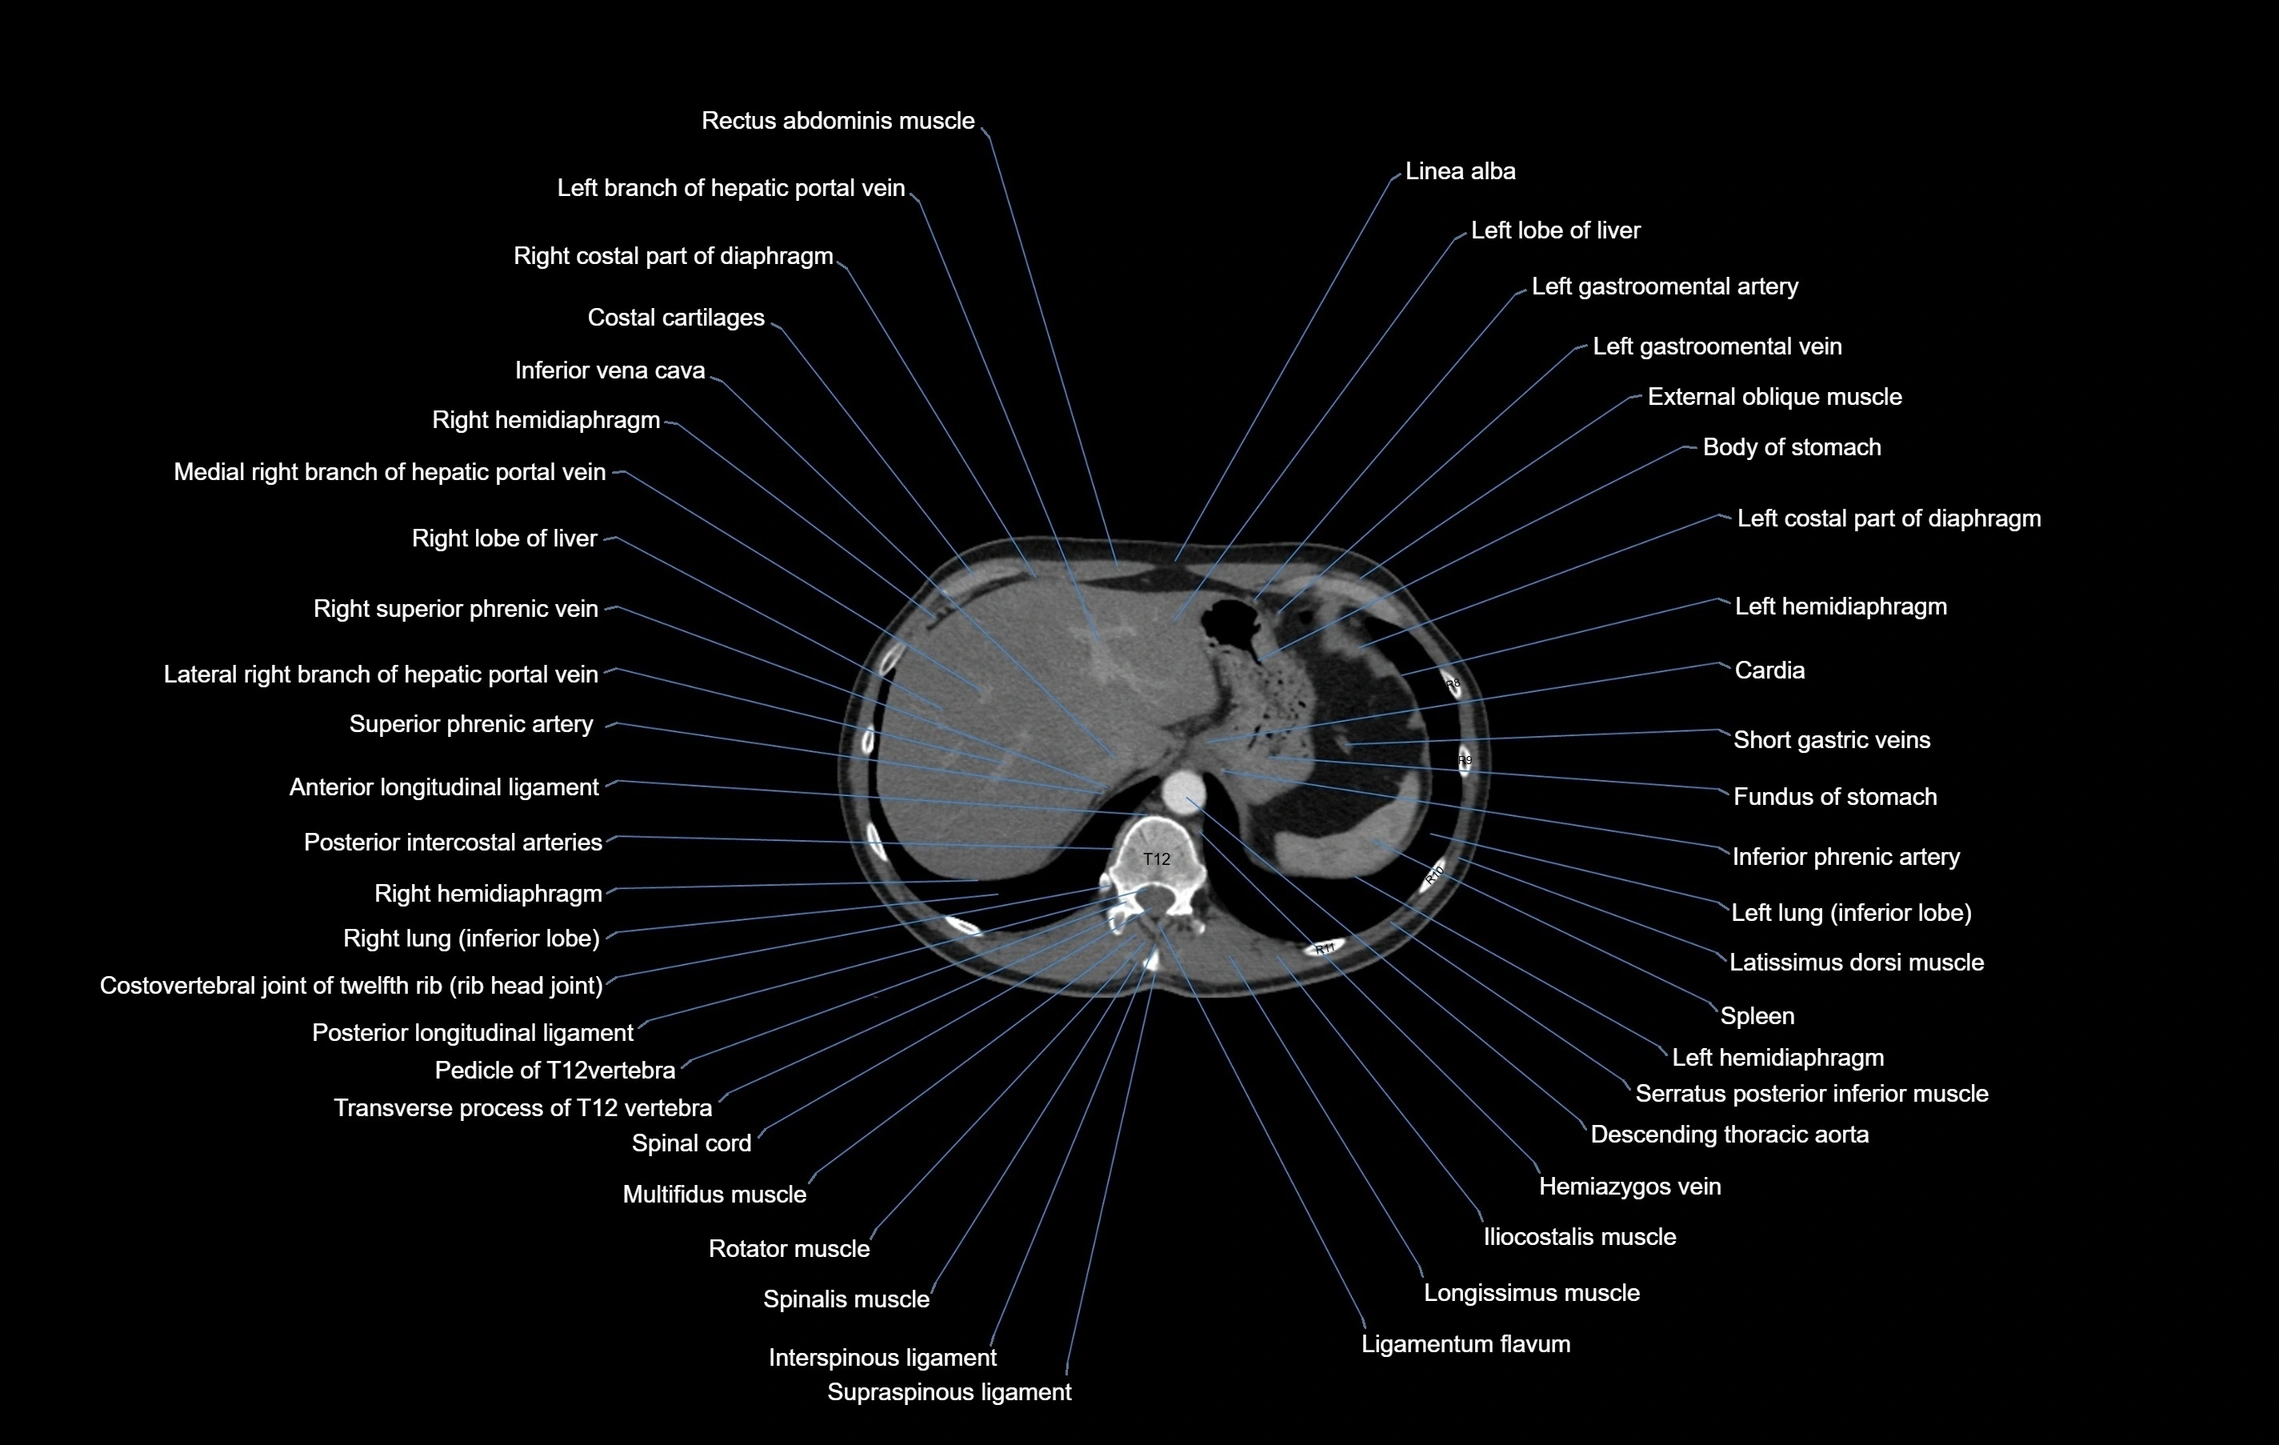

- Costal part of diaphragm

- Crura of diaphragm

- Descending thoracic aorta

- External oblique muscle

- Hemiazygos vein

- Hepatic portal vein

- Inferior phrenic artery

- Inferior vena cava

- Left hemidiaphragm

- Left lobe of liver

- Left lung (inferior lobe)

- Multifidus muscles

- Pancreas

- Right lobe of liver

- Right lung (inferior lobe)

- Serratus posterior inferior muscle

- Spinal cord

- Spleen

- Splenic artery

- Splenic vein

- Superior mesenteric artery (SMA)

- Superior phrenic artery